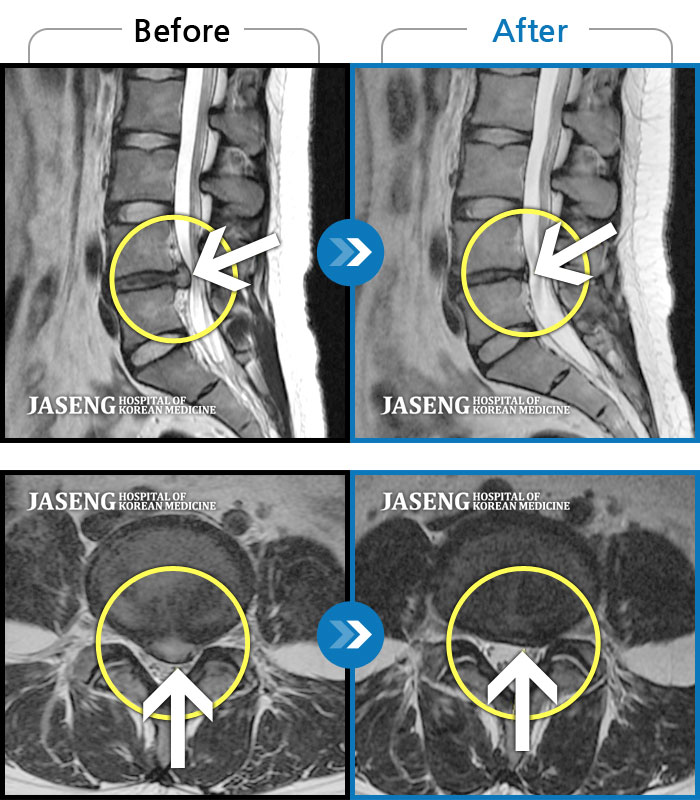

Before

After

환자에게 사전 동의를 받아 동일 조건에서 촬영되었습니다.

개인에 따라 치료 후 부작용이 발생할 수 있으니 의료진과 상담 후 치료를 진행하시기 바랍니다.